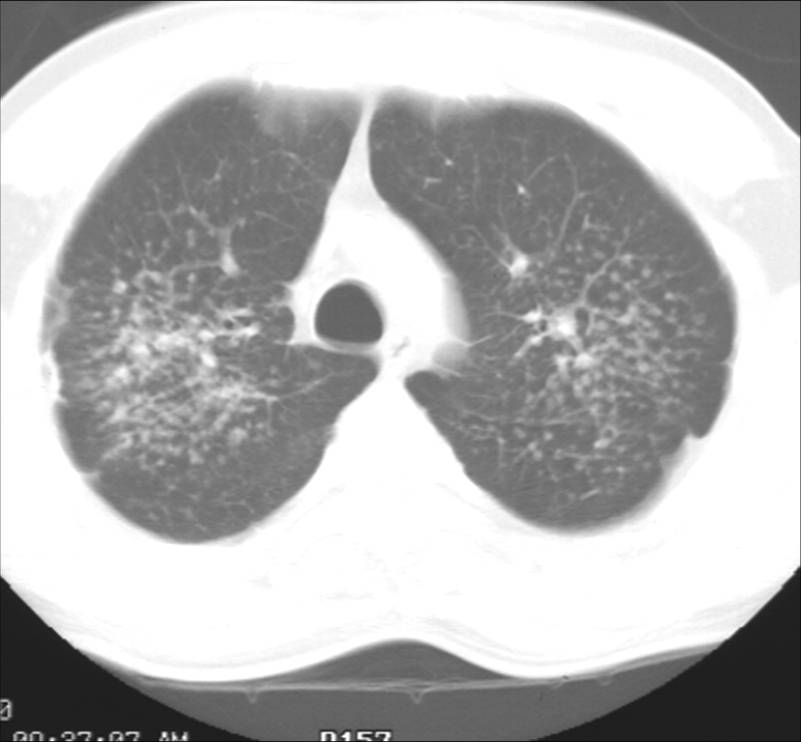

His current chest x-ray and high resolution CT scan are shown in figures 1a and 1b respectively.

Figure 1b: High resolution chest CT scan through the upper lobes demonstrating bilateral nodular disease following the peribronchovascular distribution.

Of the metals listed, only beryllium could cause both this clinical picture and radiographic appearance with these exposures. Beryllium copper alloys are used in many high technologic and electronics applications including computers. Recycling computers to reclaim copper or other metals can lead to beryllium exposure in metal recycling workers(1). Chronic beryllium disease (CBD) is a granulomatous disease with slowly progressive respiratory symptoms caused by exposure and subsequent sensitization to beryllium. The typical HRCT appearance is similar to sarcoidosis and features primarily diffuse pulmonary nodules in a peribronchovascular and/or perilymphatic distribution. The pulmonary function abnormalities include obstruction, restriction, and mixed patterns (2, 3). In this case, the patient's cigarette abuse could have contributed to his obstruction but the lack of any emphysema on the CT scan makes that unlikely to be the sole explanation. Thus, this patient had potential for beryllium exposure during his work in metal recycling and has a disease course, radiographic, and physiologic presentation consistent with chronic beryllium disease.